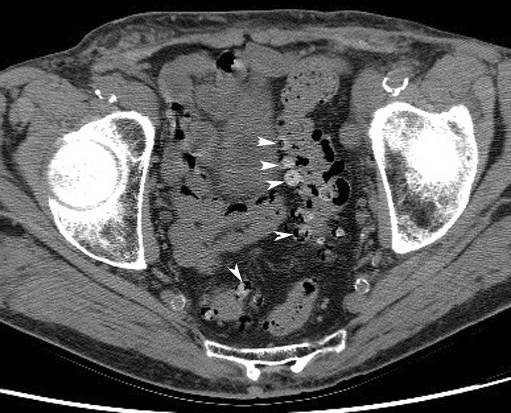

Diverticula

CT: Arrowheads point to multiple diverticula arising from the rectosigmoid.